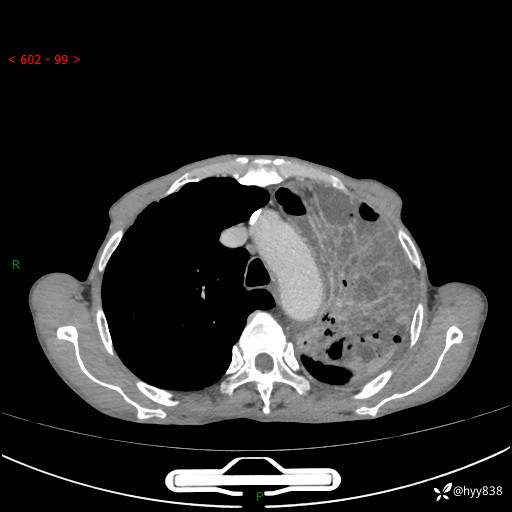

老年男性,反复咳嗽、咳痰、气喘10余年,再发3天。大叶性实变+胸膜病变-结果公布

胸部CT平扫+增强